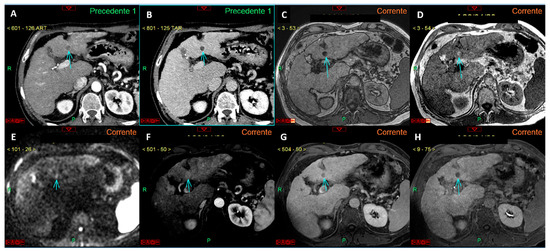

Figure 4.

Panels (A–F) represent a complete liver MRI examination with a hepatospecific contrast agent in a cirrhotic liver. Except for the T2-weighted image (A), the remaining images reveal a lesion of 4.5 mm in the liver segment VI (arrows in (B–F)) with features suspicious for HCC. Specifically, the lesion appears hypointense in the T1 out-of-phase sequence (B), shows signal restriction on diffusion-weighted imaging at a b-value 800 (C), arterial phase hyperenhancement (D), wash-out of contrast media in the venous phase (E), and hypointensity in the hepatobiliary phase (F). Panels (G–I) show a study of the same patient performed one year prior to the current examination, where no lesion in the liver segment VI was observed in the arterial (G), venous (H), or hepatobiliary (I) phases. This study demonstrates that, while the segment VI lesion has imaging features typical of HCC, it cannot be diagnosed as such according to EASL guidelines because its size is <1 cm, despite the previous negative MRI exam. However, if the new diagnostic criteria proposed by Huang et al. (see reference no. [25]) were applied, the lesion could be diagnosed as HCC due to an alpha-fetoprotein level of 37 ng/mL.